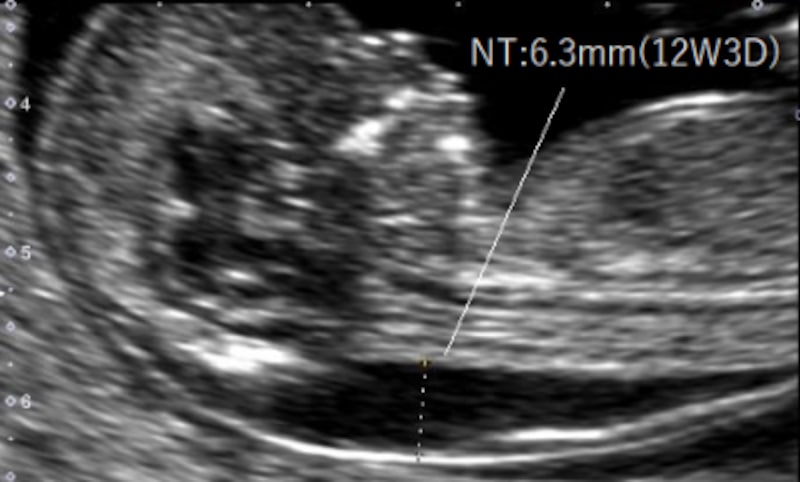

02 妊娠初期 胎児の頸部浮腫 Nt 妊娠11 13週でcheck 深谷産婦人科 医学情報

胎児の首の後ろのむくみ 浮腫 Nt とは 妊娠初期 All About

Nt Nuchal Translucency について 出生前検査 Nipt 遺伝カウンセリング 妊婦健診 エコー検査 産科 婦人科 産婦人科

胎児の首の後ろのむくみ 浮腫 Nt とは 妊娠初期 All About

胎児の首の後ろのむくみ 浮腫 Nt とは 妊娠初期 All About

胎児の首のむくみ Nt クリフム夫律子マタニティクリニック